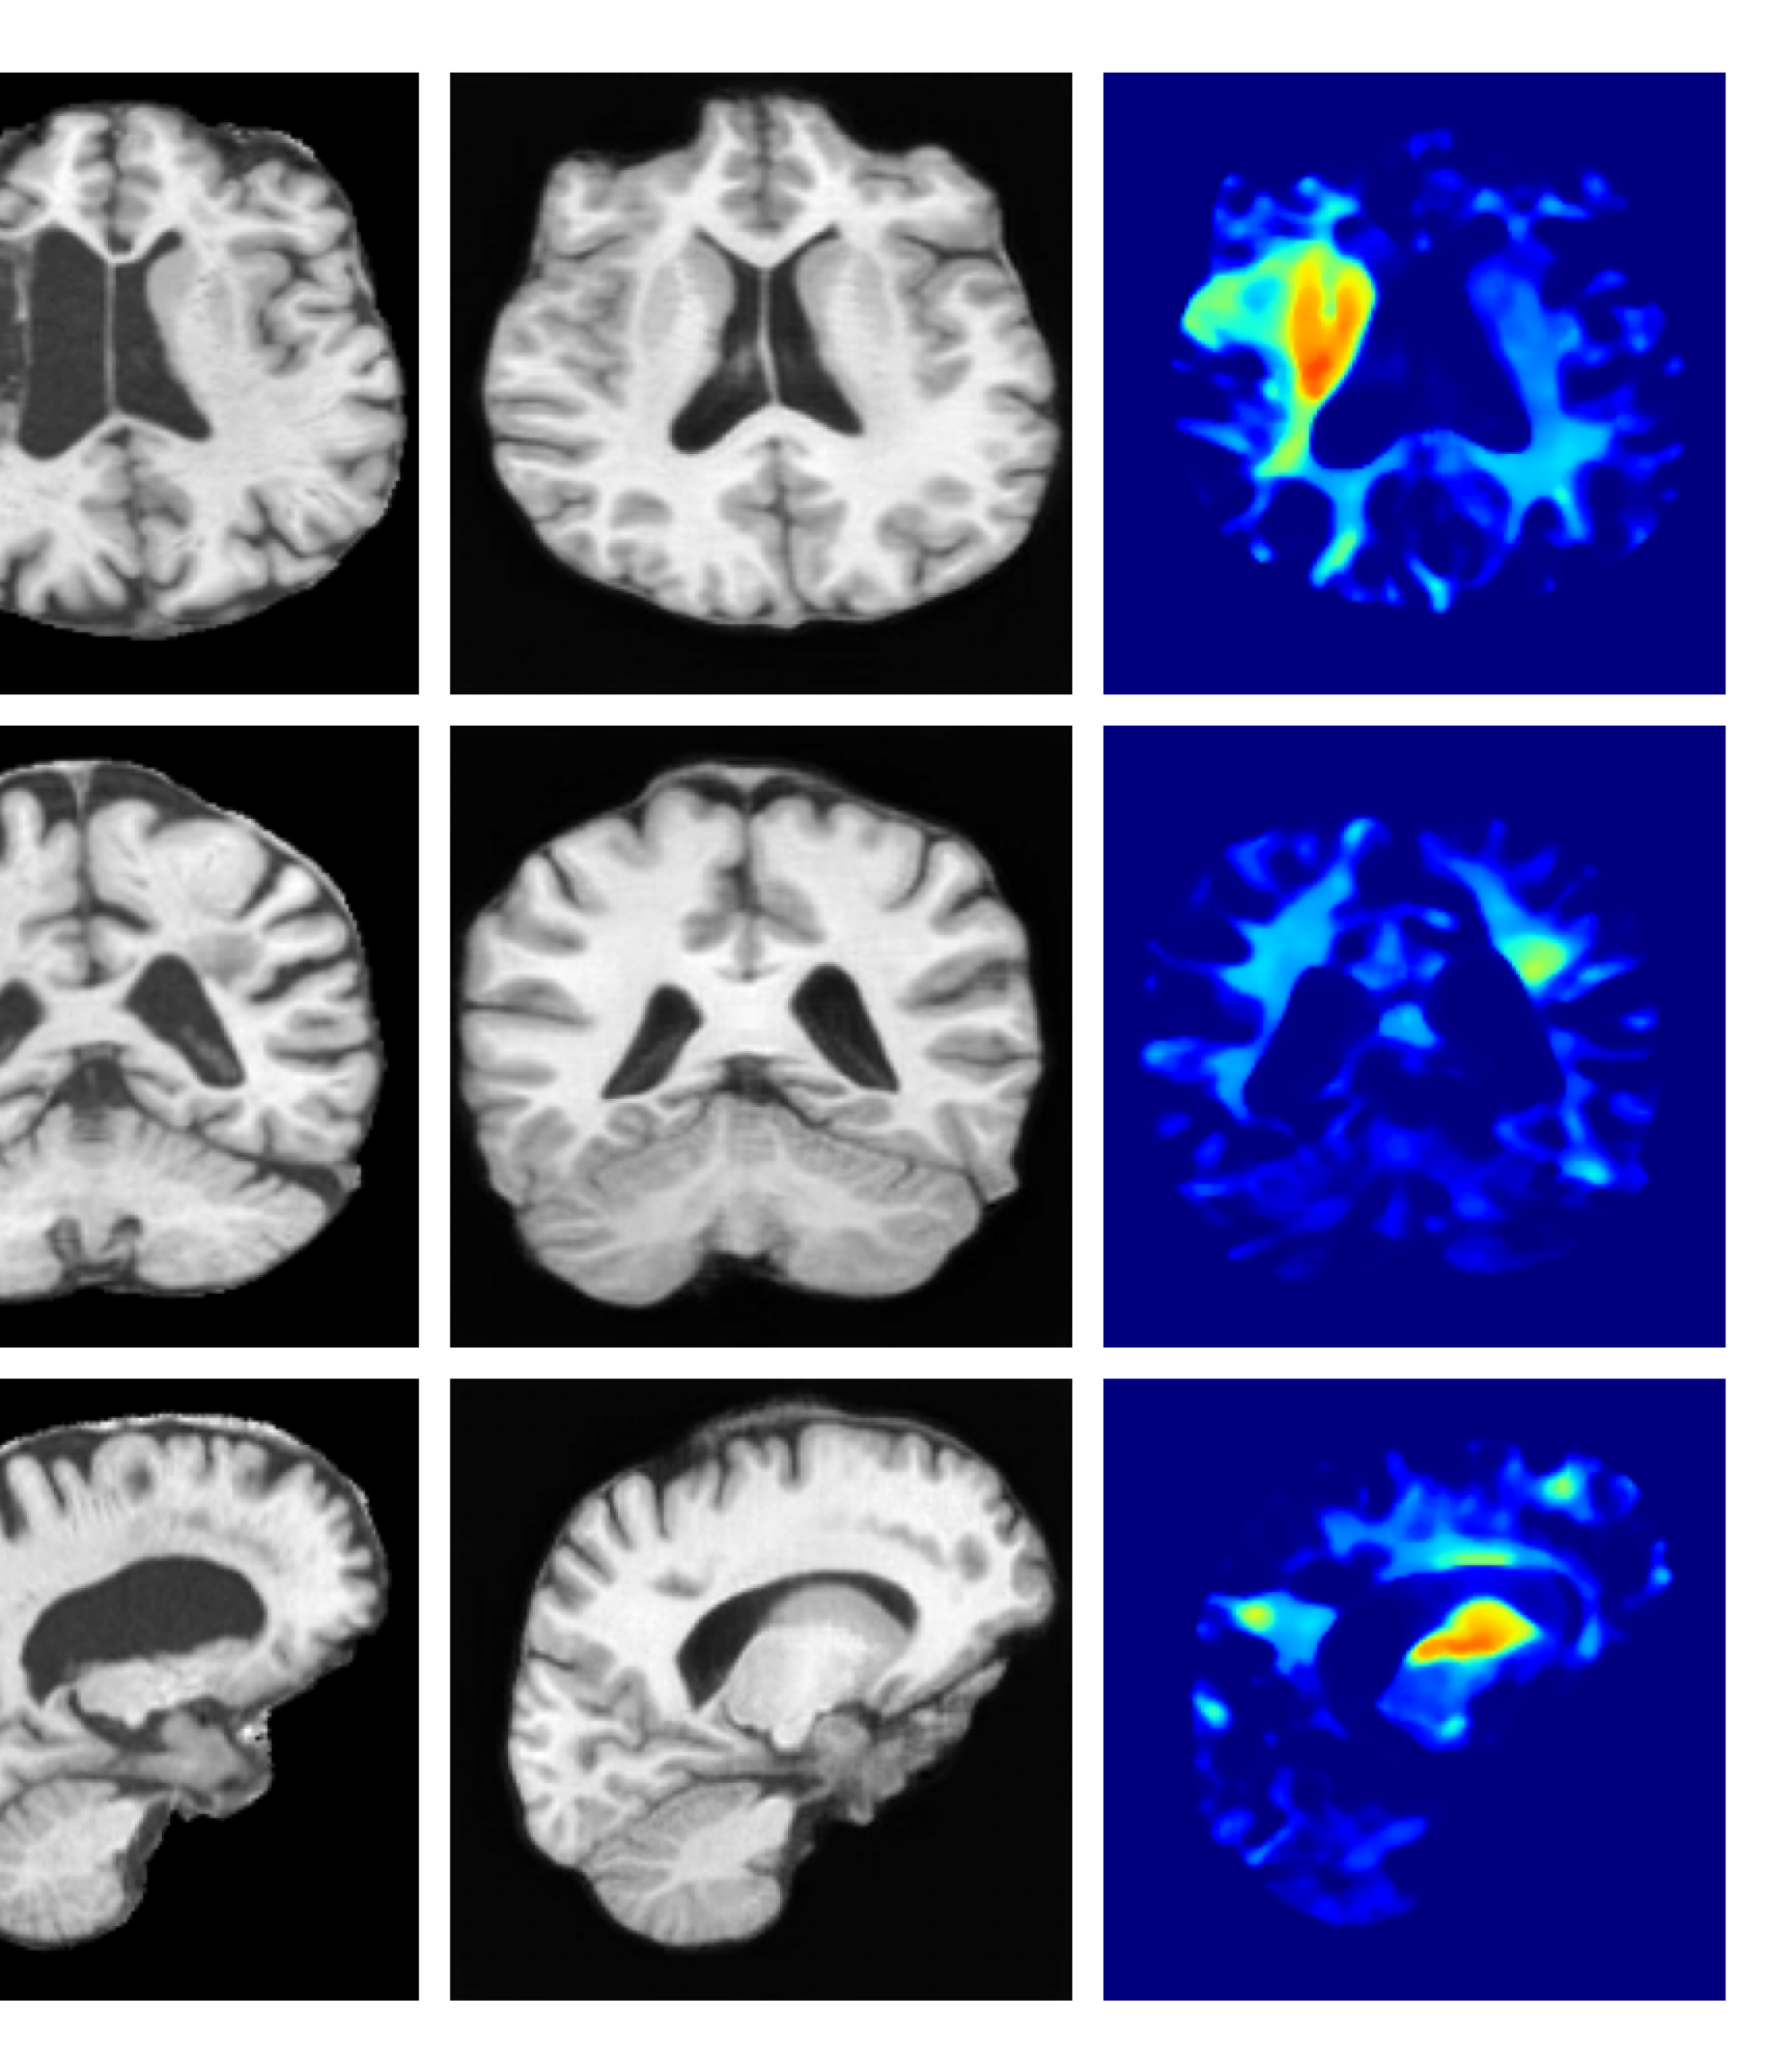

Figure 2: Example reconstructions and anomaly maps for an ATLAS test sample.

Qualitatively, the VAE generates smooth reconstructions as expected (Figure 2), leading to more false positives in healthy tissue. This corroborates the poor performance in the anomaly detection metrics in Table 1. While SynthSR effectively preserves information from healthy tissue, Figure 2 shows that it sometimes fails to fully inpaint pathological regions – particularly when these are large. Additionally, the SynthSR inpainted tissue does not appear anatomically realistic, which could limit the applicability of the pseudo-healthy images for downstream tasks. In contrast, our method produces a higher contrast anomaly map over abnormal regions, indicating superior localization of anomalies. While UNA achieves slightly better anomaly localization compared to SynthSR, it still falls short compared to our model. Although all diffusion-based methods successfully inpaint anomalous regions with realistic healthy tissue to some extent, they again do not achieve the same level of anomaly localization as our method.

In this work, we introduced a novel pseudo-disease conditioned diffusion model framework for anomaly detection in 3D pathological T1 MRI. Our model achieves state-of-the-art performance across both synthetic and real pathology datasets. The high Dice scores and low FPR in Table 1 (on par with those of a supervised approach), coupled with the high contrast anomaly map in Figure 2, demonstrate that our model effectively inpaints pathological tissue while preserving individual-level characteristics. As such, our approach to incorporating pathological images into the diffusion model training process improves the inpainting of diseased regions while preventing the loss of critical information from surrounding healthy tissue. Further work will involve applying the generated pseudo-healthy reconstructions to other downstream tasks, such as brain parcellation or tissue segmentation. Our method holds great promise in analyzing large uncurated clinical datasets with heterogeneous types of pathology.